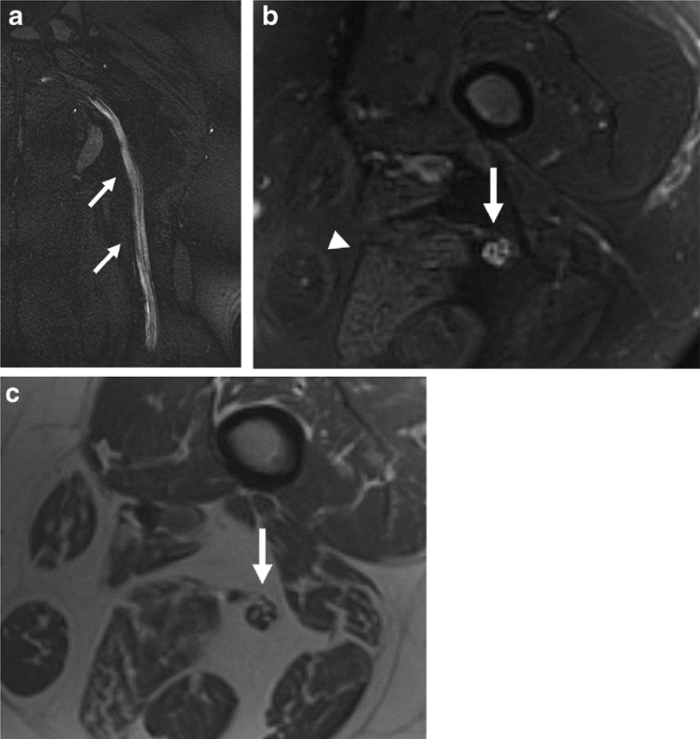

"Podríamos ver edema y cambios inflamatorios de los tejidos (líquido, hinchazón), hematomas (acumulaciones de sangre) o tejido desvitalizado (gangrena) --prosigue--. En algunos pacientes, los nervios están lesionados (brillantes, agrandados) y en otros, el problema es un flujo sanguíneo deficiente (coágulos)".

Por ejemplo, continúa, si un paciente tiene dolor persistente en el hombro que comenzó después de contraer COVID, su proveedor de atención primaria podría solicitar una resonancia magnética / ultrasonido. Si un radiólogo sabe que la COVID puede desencadenar artritis inflamatoria y las imágenes muestran inflamación de las articulaciones, entonces pueden enviar al paciente a un reumatólogo para su evaluación.

"Algunos médicos solicitan imágenes para pacientes con 'dedos de los pies COVID', por ejemplo, pero no había literatura sobre imágenes de las complicaciones del pie y los tejidos blandos de COVID --resalta--. ¿Cómo se encuentra algo si no está seguro de qué buscar? Por eso, en nuestro artículo, discutimos los diversos tipos de anomalías musculoesqueléticas que los radiólogos deben buscar y proporcionar ejemplos de imágenes".